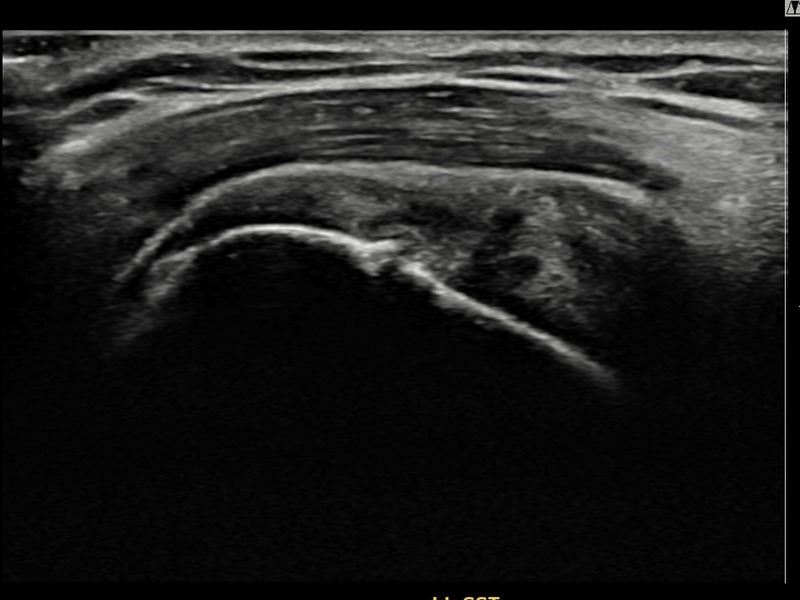

최ㅇㅇ님 · 우측 극상근건 관절면측 부분파열

우측 어깨 통증과 팔을 특정 각도로 올릴 때 심해지는 충돌 증상으로 내원하셨습니다. 초음파 검사에서 관절면측 극상근건 부분파열이 확인되었으며, 어깨인대 축소봉합술 시행 후 힘줄 구조가 안정적으로 회복되었습니다.